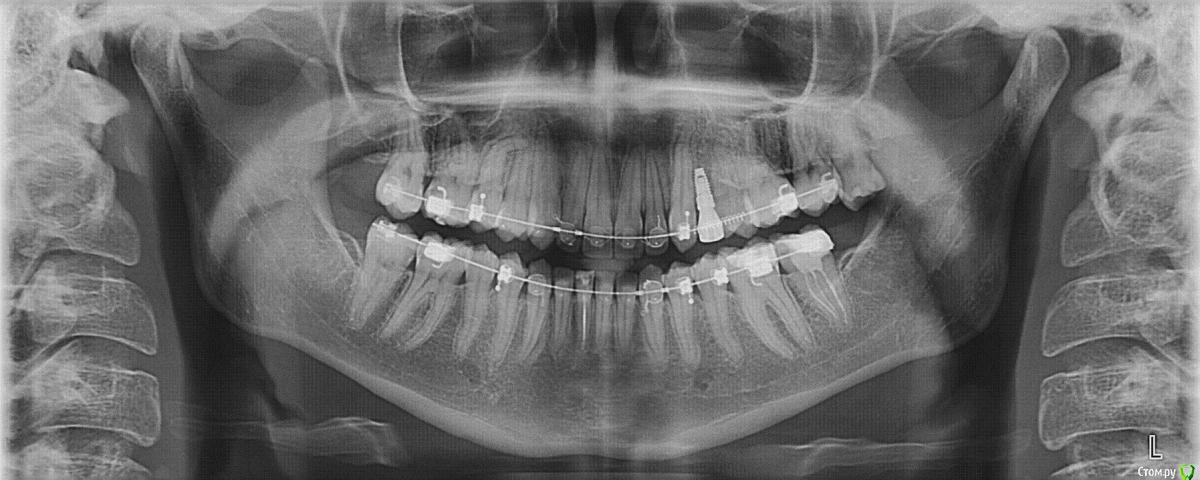

insomnia-x Опубликовано 14 декабря, 2015 Автор Поделиться Опубликовано 14 декабря, 2015 прикрепляю панорамный снимок до установки коронки Ссылка на комментарий

kozloff Опубликовано 14 декабря, 2015 Поделиться Опубликовано 14 декабря, 2015 (изменено) Хорошо бы еще увидеть прицелный снимок с коронкой.Судя по тому, что есть, проблему можно решить формированием десны на временной коронке. Изменено 14 декабря, 2015 пользователем kozloff 1 Ссылка на комментарий

Доктор Хаус Опубликовано 14 декабря, 2015 Поделиться Опубликовано 14 декабря, 2015 Я думаю здесь надо еще формировать десну . Попробуйте поговорить с Вашим доктором. К некрасивой улыбке довольно сложно будет привыкнуть. Ссылка на комментарий